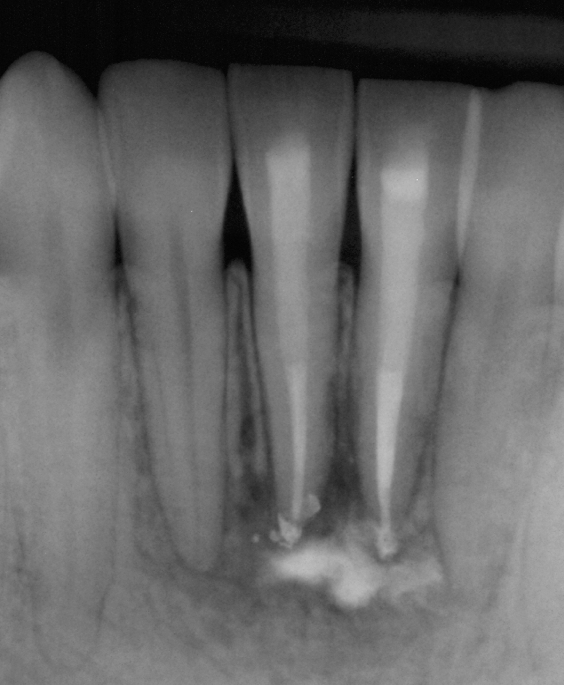

Treatment Examples

Conventional Treatment with Standard Core Restoration

Non-surgical endodontic treatment with resin core build up

Conventional endodontic treatment with alloy core build up

Conventional Endodontic Treatment with Post and Core Coronal Restoration

Conventional Endodontic Treatment/Retreatment with Prefabricated Bonded Post and Core

Conventional Endodontic Treatment with Minimal Clinical Crown: Cast Post and Core Coronal Restoration

Surgical Endodontic Treatment

Hemisection with Cast Post and Core

Surgical Exposure of ECIR with External Cervical Root Repair, Conventional RCT with Prefab Post

MB Root Amputation

Long Term CaOH Cases

12 Month CaOH Treatment

14 Months CaOH Treatment

All Treatment performed by Dr. Brian A. Christopherson